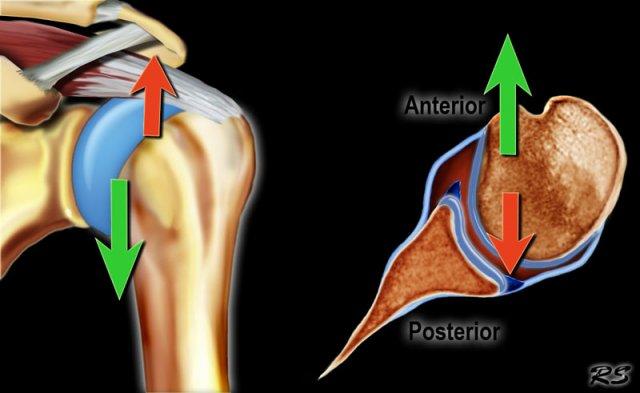

Chỏm xương cánh tay hầu như luôn bị di lệch ra trước và vào trong, xuống dưới mỏm quạ.

Trật khớp ra trước

Sự di lệch của chỏm xương cánh tay ra trước-dưới gây tổn thương bờ trước-dưới của ổ chảo tại vị trí 3 – 6 giờ (đánh dấu màu đỏ).

Đặc biệt ở bệnh nhân trẻ tuổi, điều này dẫn đến gãy xương Bankart hoặc tổn thương Bankart, là rách sụn viền trước-dưới.

Hậu quả là gây mất vững khớp và trật khớp tái phát.